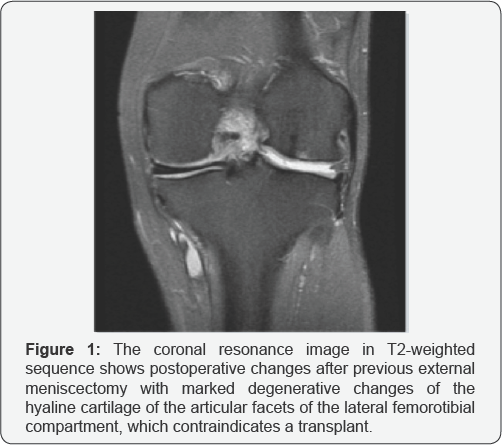

d. Major cartilage damage (advanced joint degeneration (Outerbridge> 2) (Figures 1 & 2).